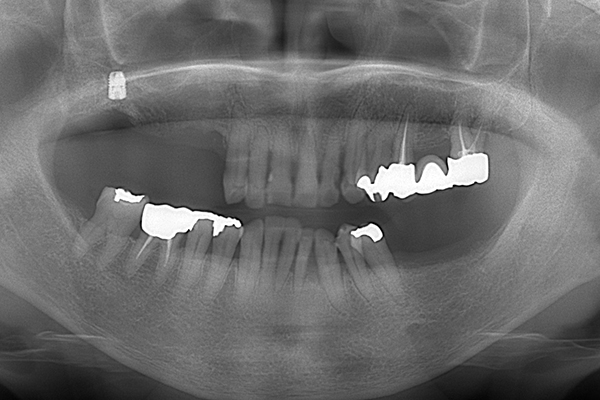

3.レントゲン診査

レントゲンで、顎の骨の厚みや、顎の関節の状態と位置を見ていきます。また、噛む力は強いのかなども診ることができます。 歯があれば、その状態も診査していきます。

ケース3(インプラントを用いた部分入れ歯)

右上と左下の歯がない方です。 上の入れ歯の安定が悪く、作り直したいとのことでいらっしゃいました。 今お使いの上の入れ歯を見てみると、口蓋部分が抜けており、安定性に欠ける構造になっていました。この入れ歯はノンメタルクラスプデンチャーといって、金属のバネを使用しない 入れ歯になります。これは見た目は良いのですが、歯への負担が大きいことと、入れ歯自体がやわらかいため、噛むには不便なことがあります。

入れ歯は極力薄くするために金属を使用しました。しっかり噛める様にするため、ノンメタルクラスプデンチャーにはしませんでした。

上の入れ歯(表)

上の入れ歯(裏)

下の入れ歯

入れ歯を入れた状態のお口の中の写真です。バネも極力目立たないように作成しています。

年齢 70代・女性

主訴 上の入れ歯の安定が悪く、作り直したい

治療期間 5ヶ月

治療費 .診査診断:55,000円

.インプラント埋入:165,000円

.アバットメント:33,000円

.義歯:330,000円

治療方針 右片側のみ奥歯がない方です。

この様な場合入れ歯は反対側に維持を求めるため、大きな入れ歯になりがちです。

そのため違和感が強いことがおおいです。

また、片側だけないですので、安定もむずかしくなります。

そこで、安定をよくするために、右の奥歯の位置にインプラントをいれて、義歯が揺れない様にすることにしました。

治療内容 レントゲンをみて最低限の長さのインプラントを右上の奥歯の位置に埋入しました。インプラントと骨の結合(オッセオインテグレーション)と歯肉の治癒を待ち、アバットメントをいれて型取りをして、入れ歯を作成しました。極力薄くするために、金属をもちいた入れ歯にしました。

特記事項 インプラントは必ず成功するというものではありません。 また治癒も人それぞれで、長くかかることもあります。 入れ歯を入れ終わったあとも、アバットメントが緩んできたり、入れ歯が歯ぐきにあたって痛いところもでてきますので、調整は必要になります。